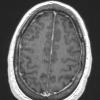

NEOPLASMS (GLIAL)

Astrocytoma, IDH-mutant, WHO Grade 2 (9)